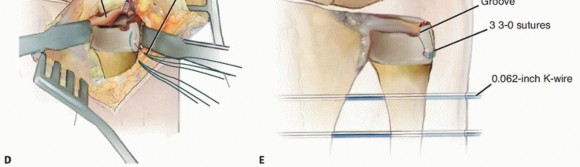

TECH FIG 2 • Open DRUJ/TFCC exposure and repair. A. Incision. B. Extensor retinaculum opened exposing fifth compartment. C. TFCC and DRUJ exposed. D. 3-0 nonabsorbable sutures placed through TFCC and ulna bone tunnels. E. Final construct demonstrating transfixation with 0.062-inch K-wires and TFCC repair.